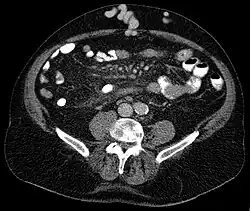

Axial CT showing portosystemic collateral circulation via the umbilical vein: caput medusae in liver cirrhosis

Caput medusae is the appearance of distended and engorged superficial epigastric veins, which are seen radiating from the umbilicus across the abdomen. The name caput medusae (Latin for "head of Medusa") originates from the apparent similarity to Medusa's head, which had venomous snakes in place of hair. It is also a sign of portal hypertension.[1] When the portal vein, that transfers the blood from the gastrointestinal tract to the liver, is blocked, the blood volume increases in the peripheral blood vessels making them appear engorged.[2] It is caused by dilation of the paraumbilical veins, which carry oxygenated blood from mother to fetus in utero and normally close within one week of birth, becoming re-canalised due to portal hypertension caused by formation of scar tissue (fibrosis) in the liver. The appearance is due to cutaneous portosystemic collateral formation between distended and engorged paraumbilical veins that radiate from the umbilicus across the abdomen to join systemic veins.[3]

In Liver Cirrhosis, the paraumbilical veins open up to transfer portal venous blood into systemic circulation. It results in caput medusae.[5]